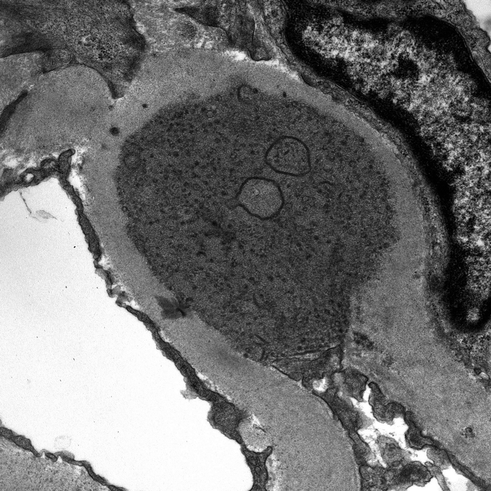

Psgn Electron Microscopy : Low Magnification Transmission Electron Micrograph Of A Glomerulus Download Scientific Diagram : Faculty of materials science & engineering.

Low Magnification Transmission Electron Micrograph Of A Glomerulus Download Scientific Diagram

Low Magnification Transmission Electron Micrograph Of A Glomerulus Download Scientific Diagram from www.researchgate.net